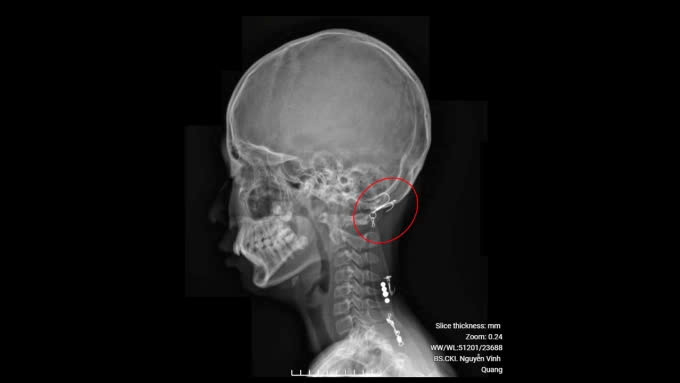

| Hình ảnh chụp X-quang cho thấy móc câu đâm vào gáy bệnh nhi. Ảnh: PKCC |

Bệnh nhi được gây tê, rạch một đường và lấy lưỡi câu ra, sau đó vệ sinh vết thương, khâu lại. Bệnh nhi được chỉ định tiêm ngừa uốn ván, xuất viện trong ngày.